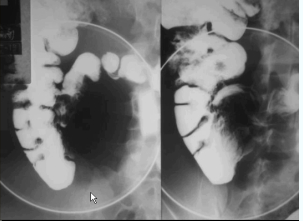

Figura 3: Série com AP, oblíquas e perfil. Fonte: Radiopaedia

4.3. Posições Radiográficas Recomendadas

| Obliqua Direita/Esquerda | Desvendar alças sobrepostas (íleo terminal) |

| Perfil (Lateral) | Estudo da valva íleo-cecal e refluxo |